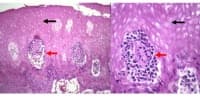

Коликвационна некроза

Когато клетките умират от некроза, те проявяват два основни вида микроскопи или макроскопски вид. Пъ...